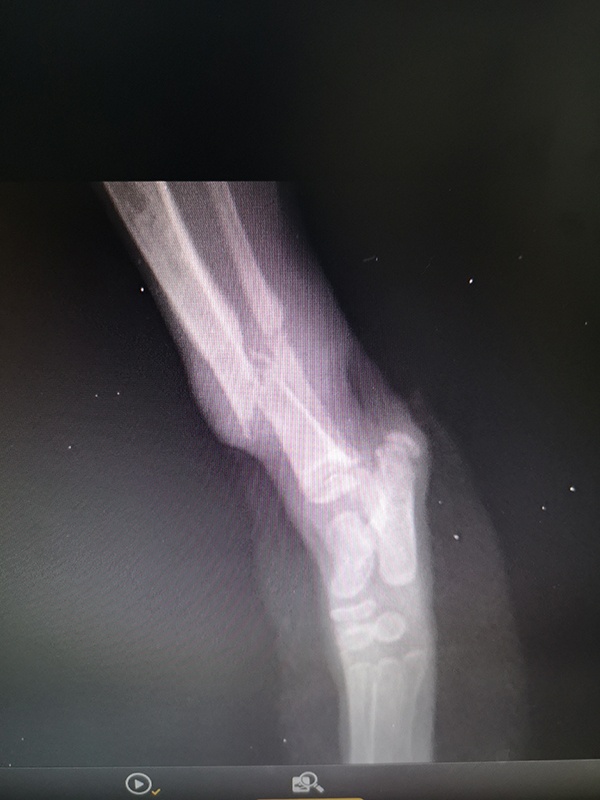

Κάταγμα σε γατάκι 0.5kg 10 ημερων

Ακολουθήσαμε ειδικό σχήμα αναισθησιολογικό ασφαλές για ένα μικροσκοπικό ασθενή. Έγινε ανάταξη του κατάγματος και σταθεροποίηση με εξωτερική οστεοσύνθεση με ήλους και εποξικό υλικό. Το γατάκι ξύπνησε αμέσως μετά την επέμβαση σε ειδικό κλουβάκι ανάνηψης και έλαβε το γεύμα του για να αποφύγουμε την υπογλυκαιμία.

Σε 3-4 εβδομάδες αν το οστό έχει κάνει την απαιτούμενη πωρωση θα ακουληθήσει αφαίρεση των υλικών.